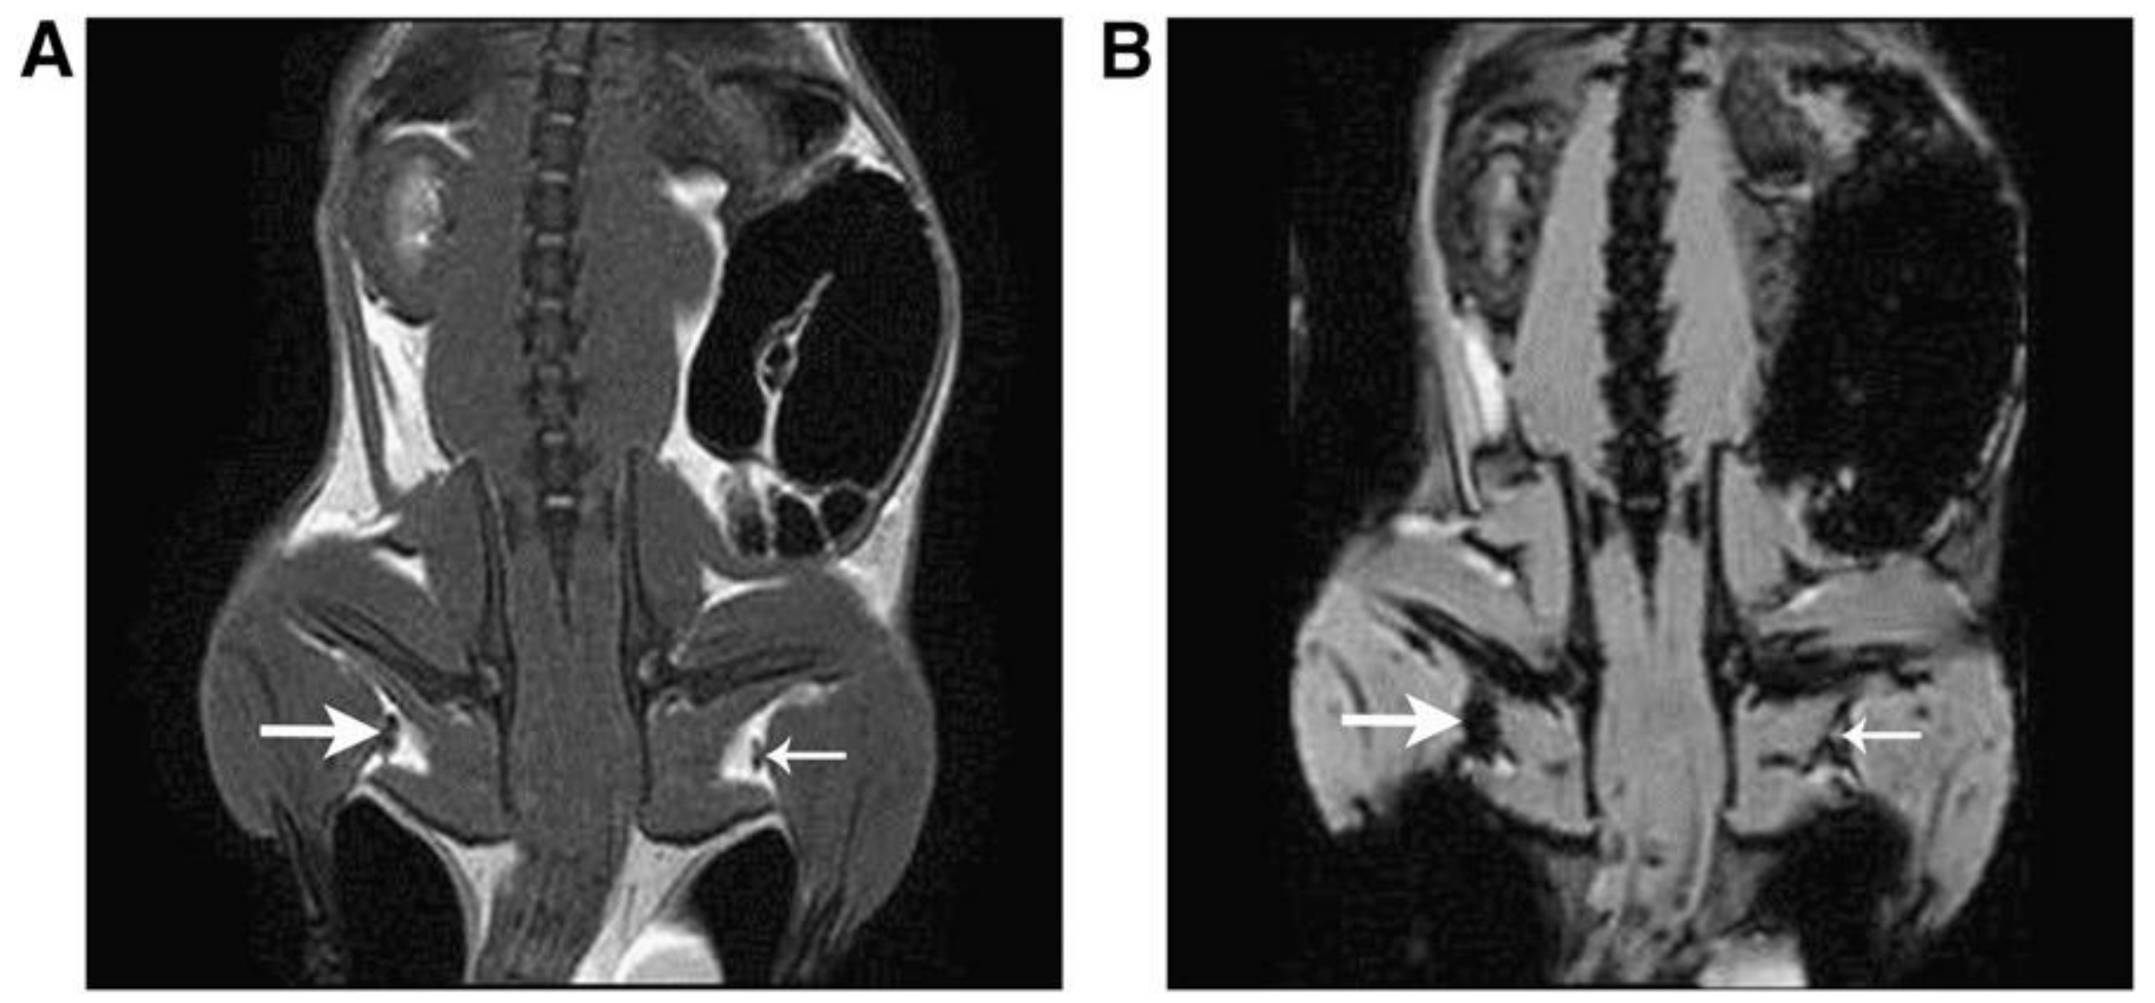

- Evertsson, M.; Kjellman, P.; Cinthio, M.; Andersson, R.; Tran, T.A.; Grafström, G.; Toftevall, H.; Fredriksson, S.; Ingvar, C.; Strand, S.E.; et al. Combined Magnetomotive ultrasound, PET/CT, and MR imaging of (68)Ga-labelled superparamagnetic iron oxide nanoparticles in rat sentinel lymph nodes in vivo. Sci. Rep. 2017, 7, 4824. [Google Scholar] [CrossRef]